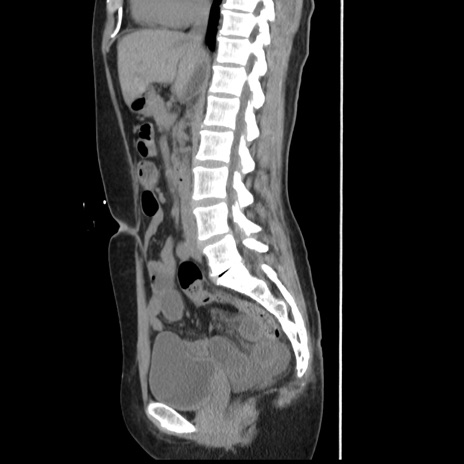

横断像

【症例】 50歳代女性

【主訴】 腹痛

【現病歴】前日生レバーを食べた。今朝に排便あり。 昼前に突然発症の腹痛を生じ、当院救急外来を受診した。

【既往歴】 子宮筋腫にてで子宮全摘後

【身体所見】 意識清明、腹部:平坦、軟、下腹部やや左を中心に圧痛・反跳痛あり、筋性防御あり

【データ】WBC 7800、CRP 0.07